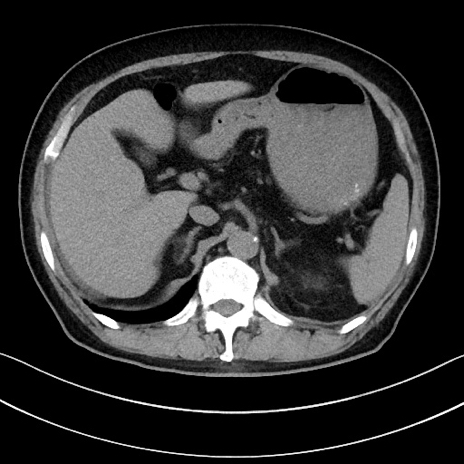

症例15(横断像)

【症例】70歳代男性

【主訴】腹痛

【現病歴】今朝から腹痛あり。全体的に痛い。特に左上の方。排ガスが今日はない。冷や汗が出る。

【既往歴】直腸癌術後

【身体所見】左側腹部〜上腹部に圧痛あり。腹膜刺激症状明らかなではない。軽度反跳痛。左下腹部に術後瘢痕あり。

【データ】WBC 7700、CRP 0.02